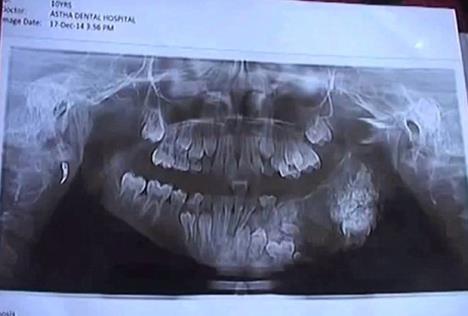

Sedmogodišnji Indijac Ašik Gavai patio je od jakih bolova u gornjoj vilici, i redovno se žalio svojim roditeljima koji su mislili da je u pitanju nešto bezazleno. Bol je postajao sve jači i jači, tako da su morali da potraže profesionalnu pomoc, piše Dejli mejl.

Sa velikim otokom na licu, došli su na pregled u lokalnu bolnicu, a njegovo stanje šokiralo je sve prisutne. Dečaku je ustanovljena neobicna dijagnoza, naime bolest koja podrazumeva specifičnu vrstu tumora koji napada vilicu i desni i izaziva pojavu dodatnih zubića koji rastu nasumice na raznim mestima u gornjoj vilici, a usledila je operacija u trajanju od 4 sata!

Operacija je uspešno obavljena u bolnici "Maharaja Yashwantrao" u Mumbaiu u Indiji."Pacijent se pojavio 5 dana pre zahvata sa gnojnim čepom i bolovima u vilici. Nakon toga isplanirana je operacija na kojoj smo odstranili 80 dodatnih zubića! Ovo je jako retko u tim godinama.", izjavili su hirurzi.